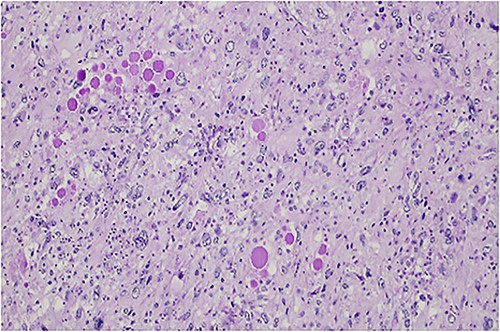

The histologic examination revealed an embryonal sarcoma (16 × 14.5 cm2) of the liver—a well circumscribed neoplasia with hyaline paucicellular areas and hypercellular areas (Fig. 4). These areas presented mainly spindle cells with severe pleomorphism as well as frequent mitotic figures, some of them atypical. Multinucleated giant cells with periodic acid-Schiff (PAS)-diastase positive hyaline globules were a habitual feature (Fig. 5) [7, 8]. Coagulative necrosis was present making up 20% of the tumor [2, 7, 8].

PAS-diastase positive hyaline globules are a main feature of embryonal sarcoma of the liver.